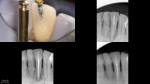

Clinicals show the access with an SS White EG-4 and a round bur which completely covers the access. File clinicials show a SSW 17/V.04 (white band) at length (20mm), am SSW 30/V.06 (blue band) (final shape) and a ProTaper (R) F1 (yellow band) that doesn't even fit in the completed access/shape.